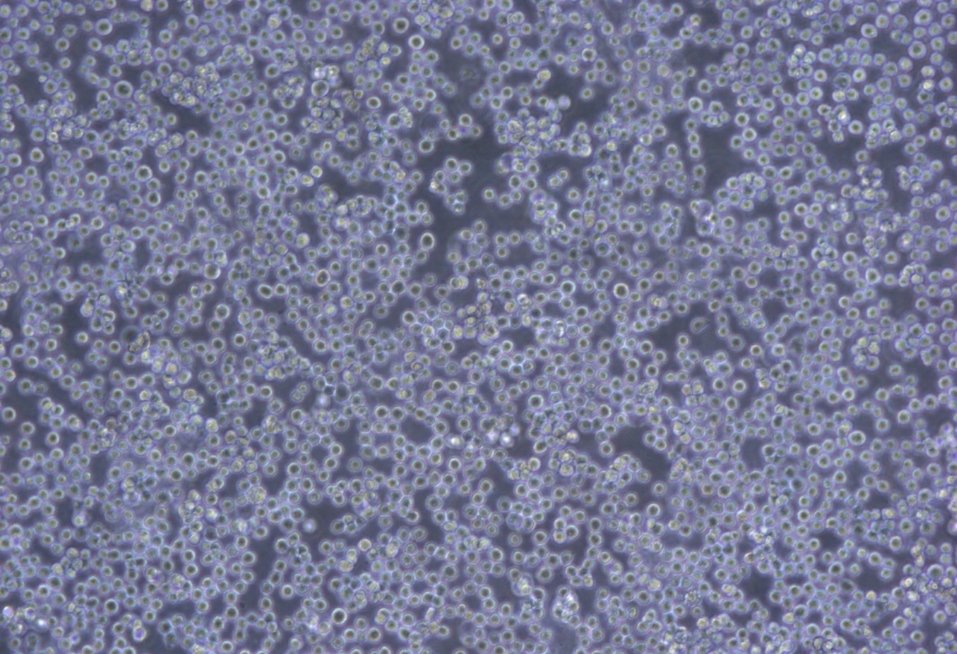

形態(tài) |

淋巴細(xì)胞樣 |

生長(zhǎng)特征 |

懸浮生長(zhǎng) |